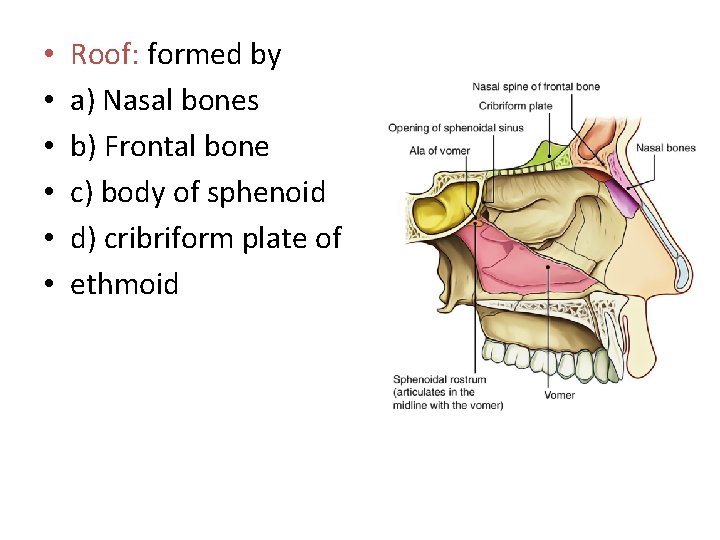

• • • Roof: formed by a) Nasal bones b) Frontal bone c) body of sphenoid d) cribriform plate of ethmoid